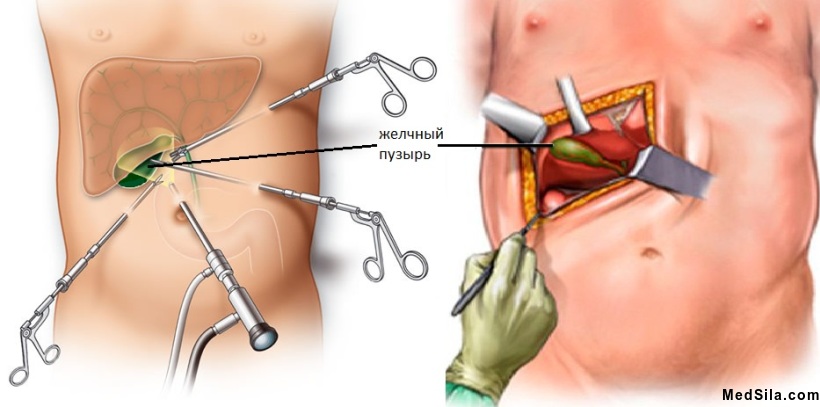

При наличии сформированных камней желчного пузыря диета и двигательный режим помогает избегать острых приступов холецистита. НЕДОПУСТИМ прием желчегонных препаратов, что может вызвать осложнение желчнокаменной болезни. Единственный способ излечения при этом - удаление желчного пузыря, как профилактика осложнений, которые могут произойти в любой момент. Операцию стараются делать в межприступный период, либо еще до первого острого приступа, когда, например, камни были выявлены случайно при профилактическом осмотре. В остром периоде операции проводятся по жизненным показаниям, почти всегда открытым способом и имеют значительно большие риски осложнений и даже смерти.